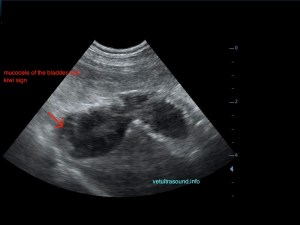

Ήπια ηπατομεγαλία με αύξηση της ηχογένειας του οργάνου, χωρίς παρουσία εστιακών αλλοιώσεων(pic.4). Πάχυνση του τοιχώματος της χοληδόχου κύστης με εικόνα βλεννοκήλης ( kiwi sign) και έντονη υπερηχογένεια στη περιοχή περί αυτού(pic.1&2). Ήπια διάταση της νεφρικής πυέλου, πιθανόν λόγω της πολυουρίας και πολυδιψίας(pic.3). Επασβέστωση στον οπίσθιο πόλο του δεξιού επινεφριδίου και αύξηση των διαστάσεών του(pic.6). Απουσία ασκιτικής συλλογής και παθολογικά διογκωμένων λεμφαδένων.

Η διάγνωση μετά τον υπέρηχο τέθηκε ως βλεννοκήλη της χοληδόχου κύστης με εικόνα χολοκυστίτιδας σε υπόβαθρο πιθανού υπερφλοιοεπινεφριδισμού. Θα πρέπει να γίνει επιβεβαίωση με αιματολογικές εξετάσεις του υπερφλοιοεπινεφριδισμού, καθώς η βλεννοκήλη της χοληδόχου κύστης είναι μία από τις επιπλοκές αυτού.